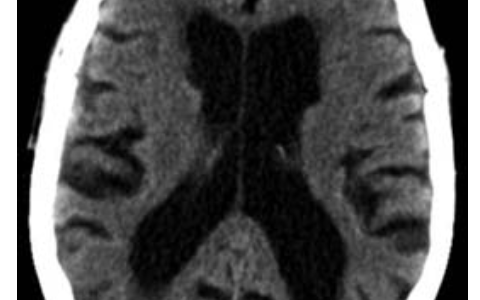

本文描述的疾病是Waldenström巨球蛋白血症,其特征是虚弱、体重减轻、血清蛋白电泳上的单克隆M峰(被视为γ区的大峰)和高黏滞综合征(表现为鼻血、头痛和视力障碍)。高黏度是由血液中b细胞肿瘤产生的大量IgM蛋白引起的。这些大蛋白质干扰微血管和细胞过程,导致血管损伤,导致头痛,因为大脑血流量受损和视力障碍,因为眼睛血流量差。此外,循环IgM蛋白可与凝血因子结合并抑制凝血因子,导致出血增加。